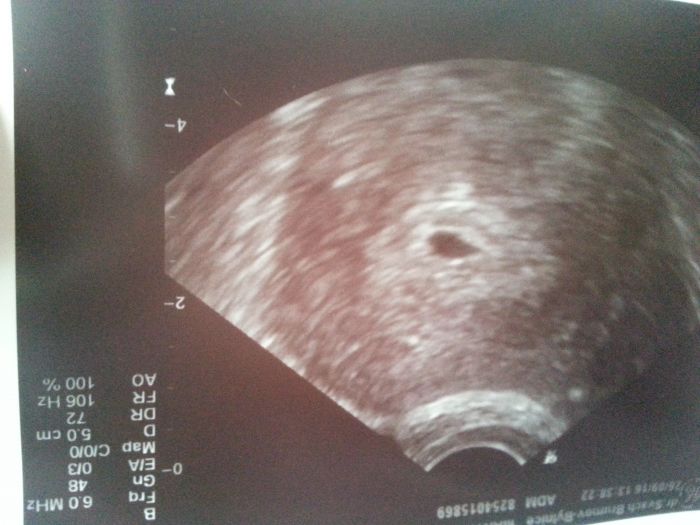

Ahoj holky, tak jsem nedopadla nic moc... dr. na ultrazvuku videl pouze gestacni vacek a nic v nem.... mela bych byt 4+6 tt., tak je prej jeste brzo nebo to muze byt zamlkle tehotenstvi.... celou cestu domu jsem brecela.... jeste, ze existujou diskuze jako tato, kde jsem se docetla, ze nekdo ma jeste i v 6. tt. prazdny gestacni vacek.... Tak snad bude mimi za 14 dni uz poradne videt.... verim tomu....